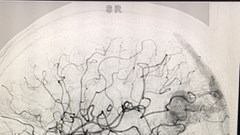

VHO- Người đang khỏe mạnh nhưng đột nhiên bạn bị đau đầu dữ dội, bất ngờ lên cơn động kinh hoặc co giật toàn thân…, đó có thể là dấu hiệu của bệnh dị dạng mạch máu não. Bệnh có nguy cơ gây tử vong cao không thể xem thường.